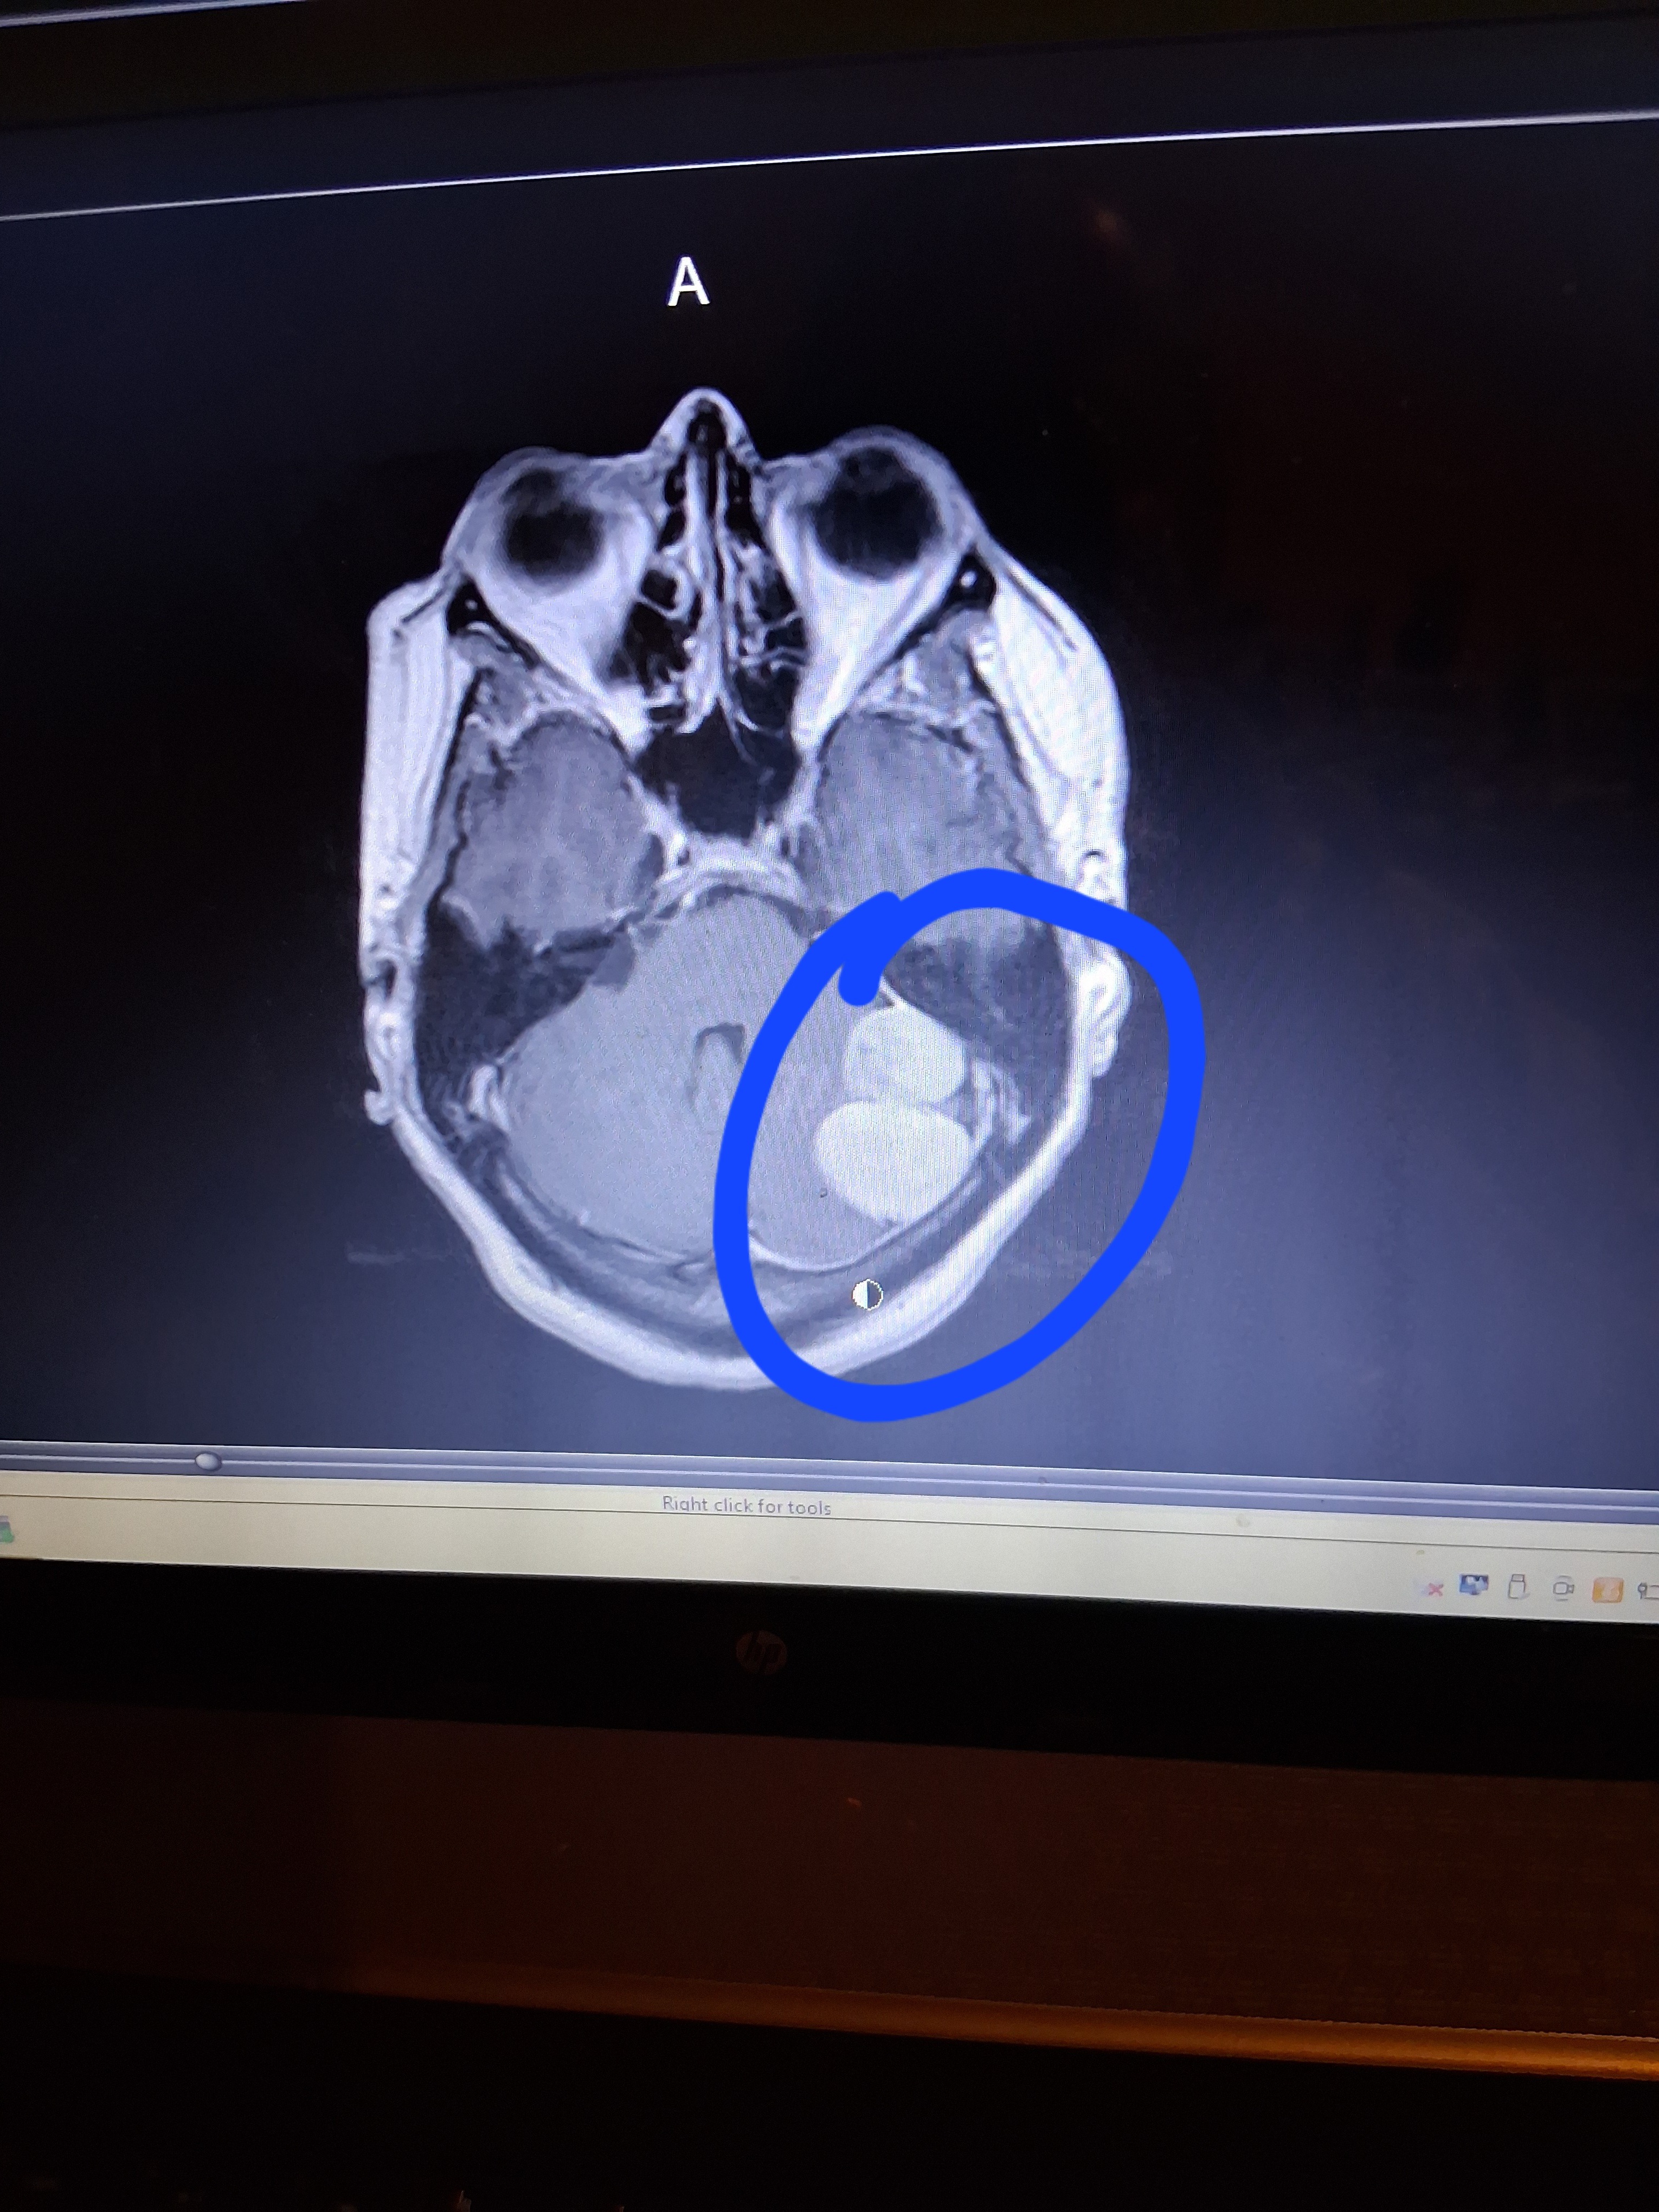

I have already 2 MRI's, and 2 C.T. scans, which showed 2 tumors, on the left side of my brain, and they are attached to one of the blood passages, on the left side of my head. I have 2 more scheduled MRI's, March 31st, and from there I will be scheduled to remove the MENINGIOMA.